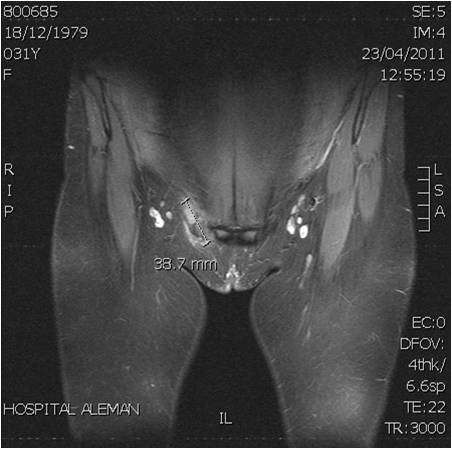

14. Hensen JH, Van Breda Vriesman AC, Puylaert JB. Abdominal wall endometriosis: clinical presentation and imaging features with emphasis on sonography. AJR Am J Roentgenol 2006;186(3):616-20.

15. Kinkel K, Frei KA, Balleyguier C, Chapron C. Diagnosis of endometriosis with imaging: a review. Eur Radiol 2006;16(2):285-98.